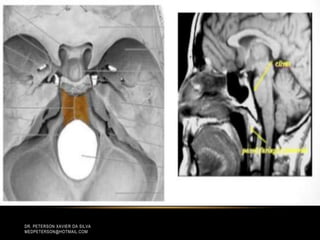

CORDOMA DE CLIVUS

• Sinal iso ou hipointenso em Tl.

• Hipersinal em T2.

• Captação heterogênea de contraste, com

aspecto de favo de mel

(áreas de hipossinal em Tl).

• Sinal isoou hipointenso em Tl. • Hipersinal em T2. • Captação heterogênea de contraste, com aspecto de favo de mel (áreas de hipossinal em Tl). ANATPAT UNICAMP DR. PETERSON XAVIER DA SILVA MEDPETERSON@HOTMAIL.COM CORDOMA DE CLIVUS

• #3 Na base do crânio, os cordomas acometem principalmente o clivus, formando lesões no interior e ao redor da sincondrose esfeno-occipital. São tumores comumente localizados na linha média, podendo apresentar extensão lateral para região parasselar e osso petroso. Extensão anterior produz lesão na região nasofaríngea, enquanto o crescimento rostral acomete a sela túrcica e a região parasselar. Pode haver envolvimento do forame magno.

• #9 • Sinal iso ou hipointenso em Tl. • Hipersinal em T2. • Captação heterogênea de contraste, com aspecto de favo de mel (áreas de hipossinal em Tl).

• #11 • Sinal iso ou hipointenso em Tl. • Hipersinal em T2. • Captação heterogênea de contraste, com aspecto de favo de mel (áreas de hipossinal em Tl).

• #13 Caracterizam-se por massa lobulada de consistência amolecida, coloração acinzentada, localmente agressivos, com intensa infiltração óssea (lesão lítica). Por esse aspecto, a neoplasia acomete predominantemente o espaço extradural, podendo, no entanto, apresentar, em alguns pacientes, envolvimento intradural. • Sinal iso ou hipointenso em Tl. • Hipersinal em T2. • Captação heterogênea de contraste, com aspecto de favo de mel (áreas de hipossinal em Tl).